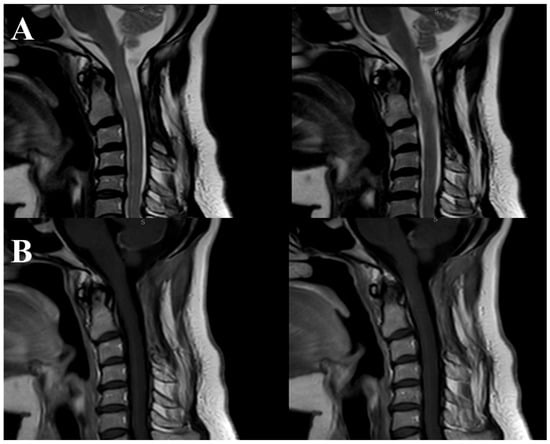

The surgery concluded without complications or neurological deficits. Postoperatively, the patient underwent an MRI that indicated the absence of residual lesions (Figure 6).

Figure 6.

Sagittal MRI sequences showing the postoperative outcome. Image (A) represents T2-weighted MRI demonstrating the absence of residual lesions after the surgical procedure. Image (B) showcases T1-weighted MRI confirming complete resection of the lesion.

At the six-month and two-year follow-ups, there was a remarkable improvement of right hemiparesis, and the patient was able to walk without assistance.